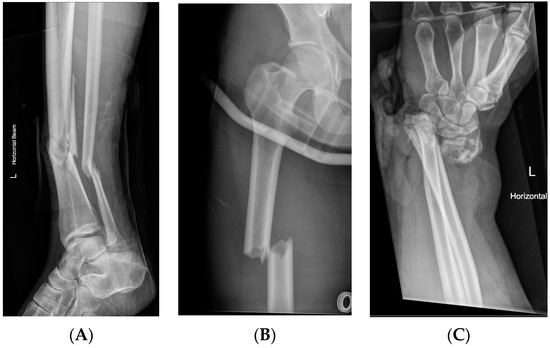

| Lower Limb Injuries | 31 | ||

| Tibial shaft | 8 | 5 | 3 |

| Fibula | 4 | 4 | 0 |

| Ankle | 3 | 1 | 2 |